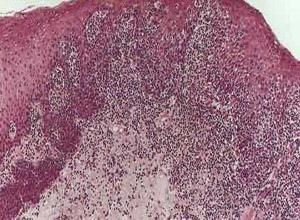

真菌直接鏡檢陽性為診斷真菌病的重要條件,可能時並作真菌培養,培養可確定致病真菌之種類。治療方案